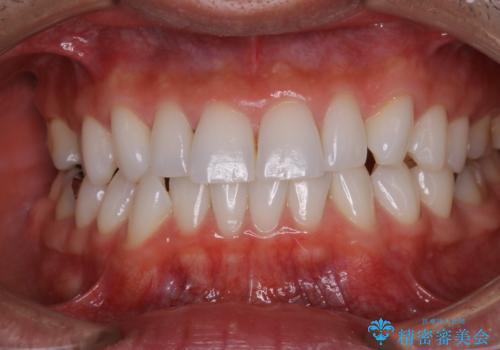

全体的な治療の開始前に着色取り